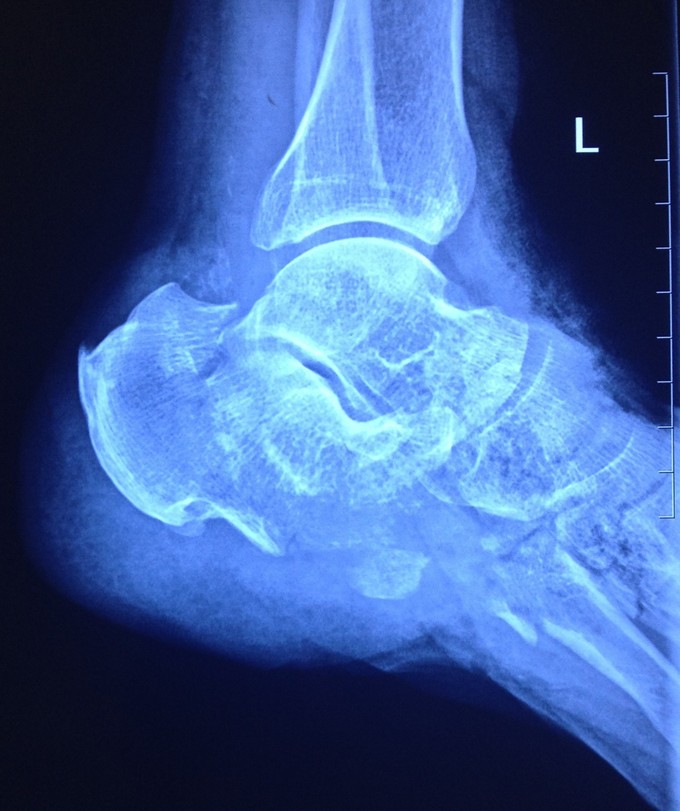

查体 辅查

神清,贫血貌,足畸形、毁损。

诊断:足挤压伤、毁损伤。多发骨折,血管神经肌腱损伤。 急诊行再植术。术中吻合足背动脉、大隐静脉。术后前足血运较好,第1趾皮温低,余四趾皮温尚可。足背皮肤血运不良。